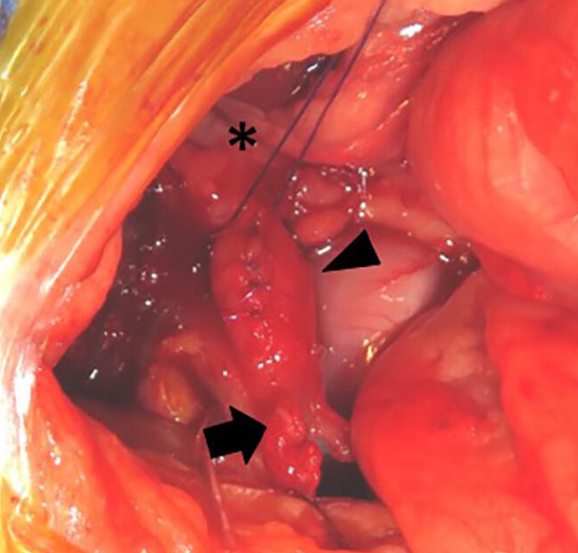

이번에 나온 논문은 담낭이 선천적으로 발생하지 않은 즉, 담낭이 없는 고양이에서 담석이 발생하고 이로 인한 자극으로 담도가 파열한 증례를 보고하고 있다.

의미를 둔다면 담낭이 발생하지 않은 증례에서 담석이 잘 발생하는 연관성에 대해 언급하고 있으니

담낭무발생 증례에서는 담낭의 결석 및 이로인한 담도의 파열 가능성에 대한 고려를 해야 한다는 말로 해석하면 된다.